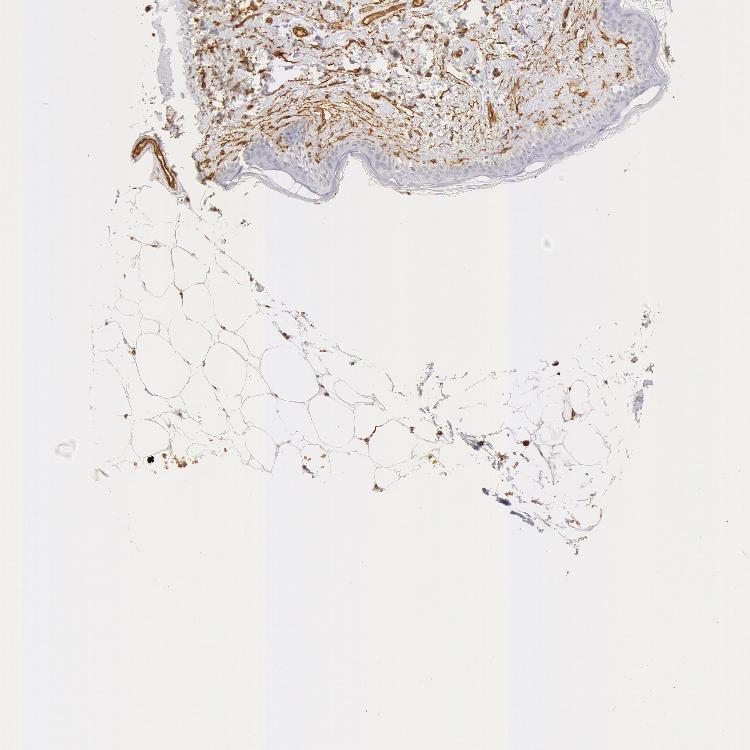

SKIN 1 - Antibody stainingi

Antibody staining in the annotated cell types in the current human tissue is reported as not detected, low, medium, or high, based on conventional immunohistochemistry profiling in selected tissues. This score is based on the combination of the staining intensity and fraction of stained cells.

Each image is clickable and will lead to virtual microscopy that enables deeper exploration of all samples and also displays staining intensity scores, fraction scores and subcellular localization as well as patient and tissue information for each sample.

Antibody HPA019206Antibody CAB001707

Endothelial cells -High

Fibrohistiocytic cells -High